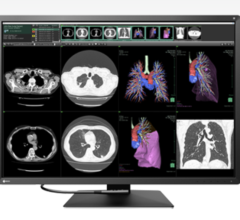

Radiology departments have many different needs and face a wide variety of challenges that can impact their departments ...

Bayer Radiology’s Barbara Ruhland and Thom Kinst discuss how radiology departments can address the many different ...